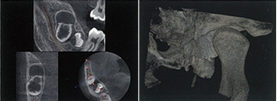

歯科用3D CTスキャンを導入しました

治田歯科医院では株式会社ヨシダの歯科用CTの『エクセラ スマート 3D』を導入しました。

今までのレントゲン診断では、二次元でしか撮影ができませんでしたが、エクセラ スマート 3Dでは今までの2D撮影に加え、立体的(三次元的)に画像を撮影できるのが大きな特徴です。

歯科用CTは、これまでの医科用CTと比べより精密な情報を必要とする歯科専用に開発されたCTです。また、医科用CTと違い、立ったままで撮影が可能で、撮影時間も8秒と短くて済む為、撮影時の患者様の体への負担が少ないのが特徴です。また、被曝線量も従来のレントゲンや医科用CTに比べて約1/10ときわめて少なく、安心して検査を受けていただくことができます。

これまでの2D撮影では一定方向からの画像しか確認できませんでしたが、3D撮影のCTでは、見たい箇所の縦方向、横方向、真上等の輪切りの画像を同時に確認できますので、厚みや骨密度等お口の中の情報がより詳細に得られ、それにより、これまで以上により正確に患部の状態を把握できるようになり、患者様に精度の高い、安全で確実な歯科医療を受けていただけます。インプラントや歯根治療や歯周病治療等の高度な治療にも大いに威力を発揮します。